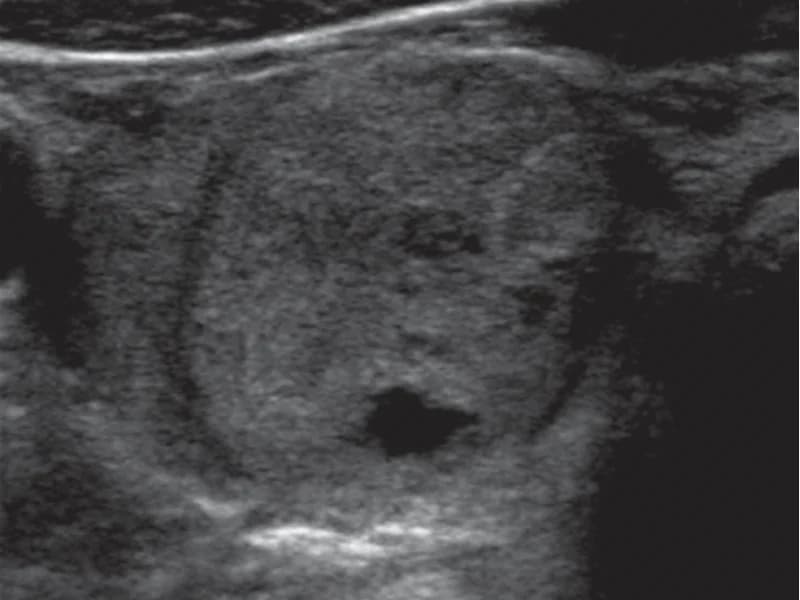

- Surgiram características novas no ultrassom (calcificações, fluxo interno)

Em nódulos menores que 2 cm, a PAAF pode não ser nem necessária, dependendo das características no ultrassom (classificação TI-RADS baixa). Quando indicada e bem feita, o resultado Bethesda II é confiável.